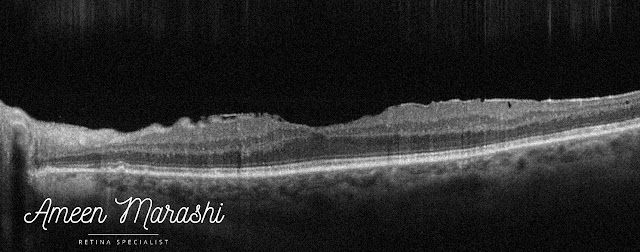

OCT features a hyperreflective band covering the inner retinal layers, causing minimal disturbance of inner retinal tissues.

| OCT cross-section shows epiretinal membrane |